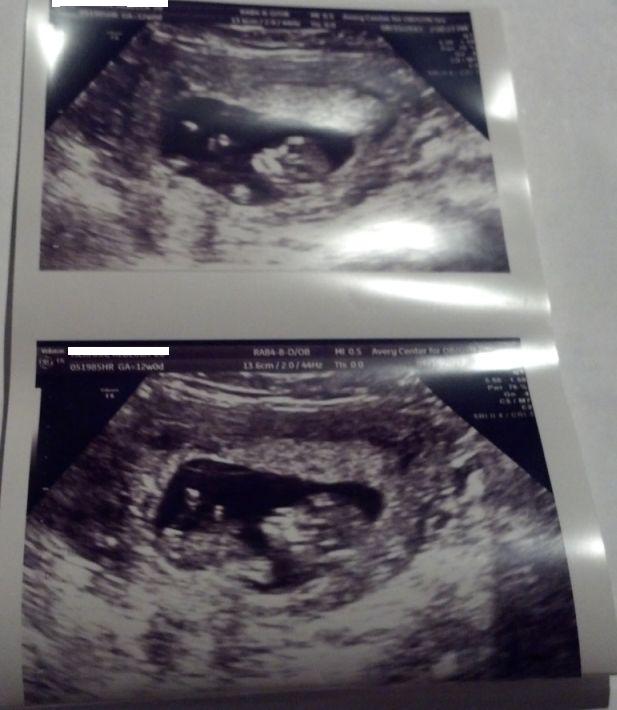

I did PGD for a girl, but for some reason I am so nervous about an opposite. These were taken today at 12w0d. The baby was moving around a lot, and I'm not sure if any of these even show a nub:

Attachment 13151

There is a really girly nub in the second picture!

Girl nub, second shot (I think, I zoomed in and I think that's what it is).

Yeah, the second picture was the one where I was thinking maybe girl nub or maybe not a nub at all... but I'm relieved there's nothing that screams "boy"